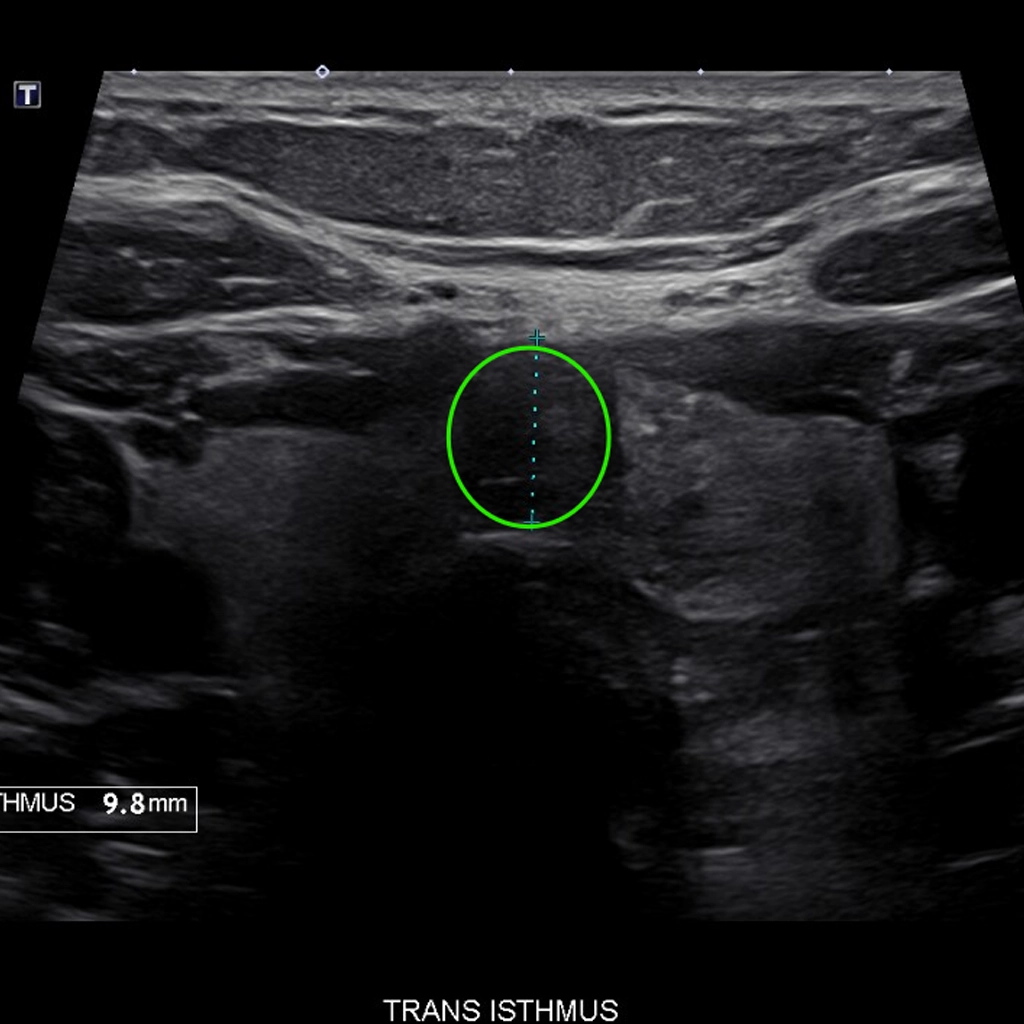

At 6 weeks, the nodule had shrunk ~70% to the size of a pea.

Natalie’s Story

Natalie, a lifelong singer, noticed she could no longer hit her high notes. She felt a thyroid lump pressing on her throat and voice box. An ultrasound confirmed an isthmus thyroid nodule the size of a small grape. The team at NSVI shrunk her thyroid through a minimally invasive procedure called Thyroid Radiofrequency Ablation. Within days, Natalie felt relief from her previous throat pressure. At 6 weeks, the nodule had shrunk 70% and down to the size of a pea. She could sing the high notes again! Plus, she had no scar and didn’t have to go through surgery.